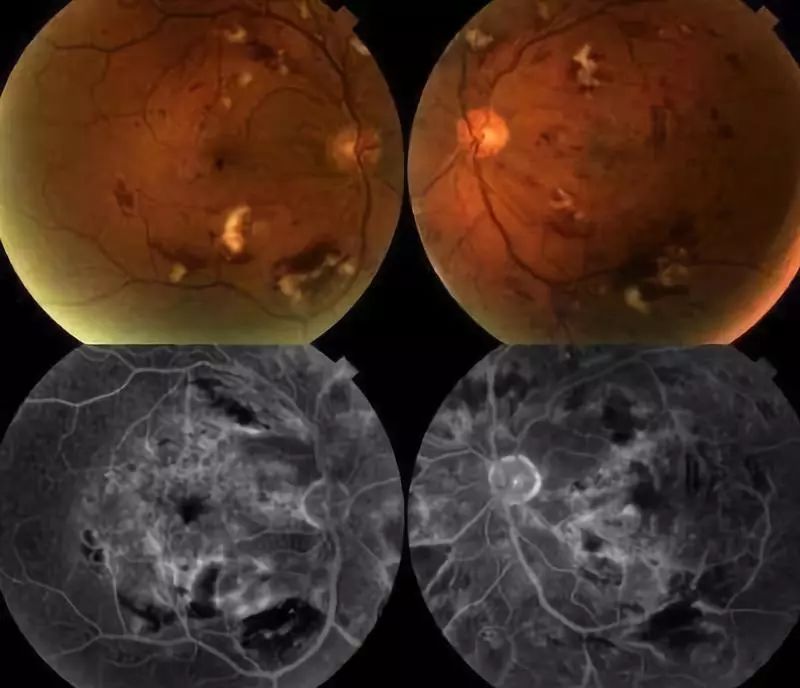

放射性视网膜病变临床变异较大,但发病呈剂量相关的特点。轻微的放射性视网膜病变的早期临床特点可以见到眼后极部出现分散的小的毛细血管阻塞病灶,病灶周围的毛细血管不规则扩张,严重的眼底有广泛的毛细血管闭锁和视网膜血管异常,可以导致黄斑水肿、渗出和视力下降。

放射性视神经病变是一种迟发的进行性的视力急剧不可逆下降的疾病,临床表现为视神经损伤、视力下降、视野缺损,视野缺损的类型由视神经不同部位的损害而定,严重者完全失明。其本质也是一种缺血性视神经病变。

三、放射性眼部血管损害的继发改变

上述损害中,不可忽视的就是血管的损害,除了引起组织缺血坏死之外,还会诱发新生血管的形成。虹膜、房角的新生血管会收缩,引起房角功能下降甚至房角关闭,导致新生血管性青光眼。而眼底的新生血管非常脆弱,一出现则非常容易继发出血。

我们常把眼球比作相机,晶状体类似于镜头,而视网膜类似于底片,视神经相当于图像数据传输工具,镜头是可以换的,而底片、传输工具这类神经组织,一旦损伤则是不可逆的。所以上述的放射性视网膜病变、视神经病变、继发新生血管性青光眼等,其病损常不可逆。